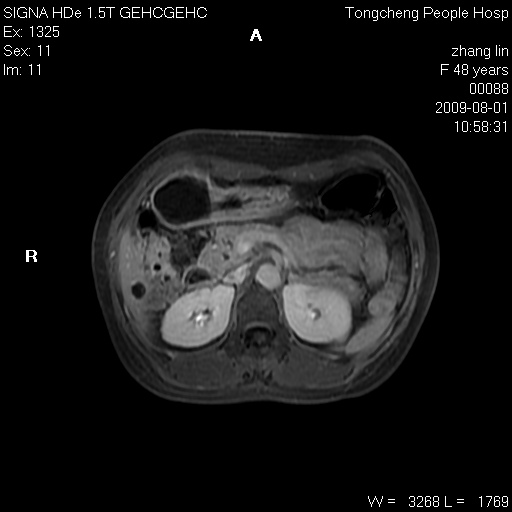

女,48岁。健康体检,彩超发现右肾占位性病变。平素健康。

临床诊断:右肾占位性病变,性质待定(囊肿?肿瘤?)。

上中腹部mr平扫+增强扫描,图像如下:

右肾上极见一类圆形病灶,t1wi呈等信号t2wi呈等高混杂信号,三期增强无强化,边界清---考虑囊肿出血。

同反相位均表现为等信号,病变无强化,考虑含蛋白的囊肿可能,弥散加权相或许有些帮助,

慢性胆囊炎